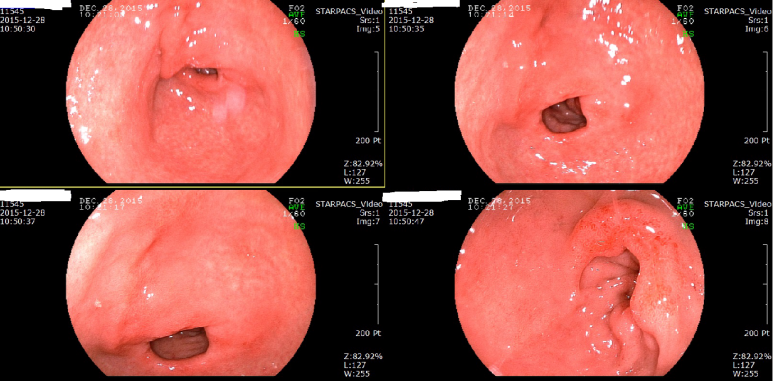

상기 검사 환자 40대 초반 2년전 초진 흡연 (-) BMI 32.5 TIA(일과성뇌허혈 증상으로)로 대학병원에서 항혈소판제, 혈압약, 고지혈증 약 복용중 1촌 뇌경색 기왕력, 대장암 기왕력 진료실 혈압 146/88, 가정혈압 수축기 120대 내원 수개월 전 타내과 위내시경 소견, 헬리코박터 양성 1년전 헬리코박터 제균

수개의 용종을 용종 절제술로 제거함

위내시경 추적; 아물어 가는 식도 미란성 변화

최근 음주를 많이 해서인지 발적, 미란성 변화 있으나 헬리코박터에 의한 만성 표재성 위염 소견은 의심되지 않음

장상피 화생 소견 있으며 조직검사상 일치함

; 요소호기검사 내시경 소견상 헬리코박터 제균되었을 확인함